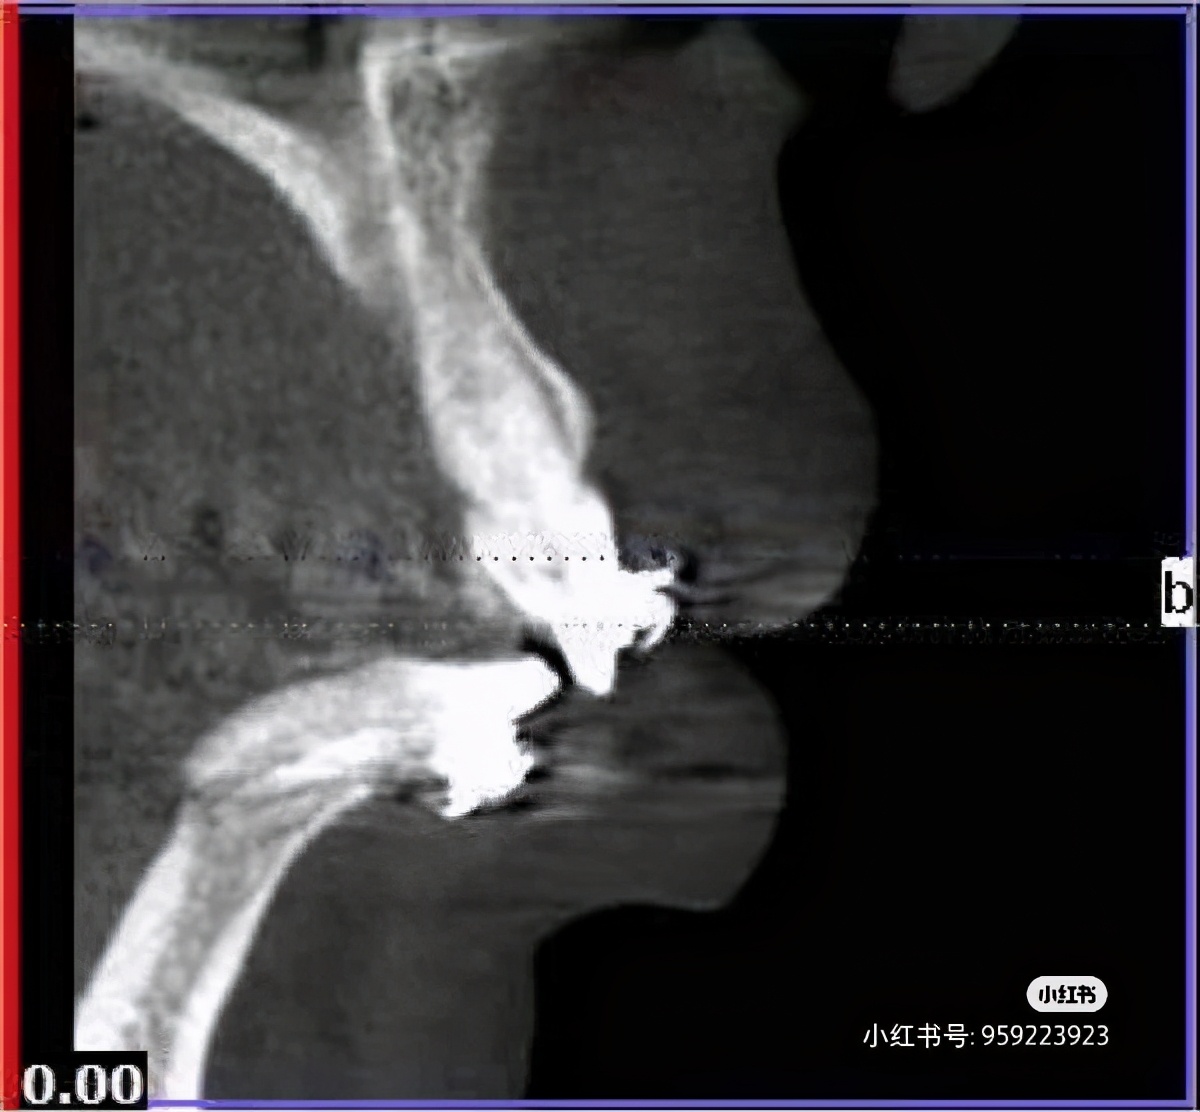

医生说我的牙齿基本可以宣布死亡了呀,我的下牙成水平状态,牙根脱离骨头,甚至种植医生告知,我连种植的机会都没有,看看正畸医生能否拯救一下。医生建议我去上海九院,这里实在不敢接手。

于是我奔赴九院,九院专家大吃一惊说第一次见到舌侧骨开窗,还让专家开了眼界。

牙齿必须二次正畸,正颌、二次正畸风险也很大,我要面临正畸期间牙齿脱落、疼痛、吸收、等一系列问题,我真的犹如晴天霹雳。